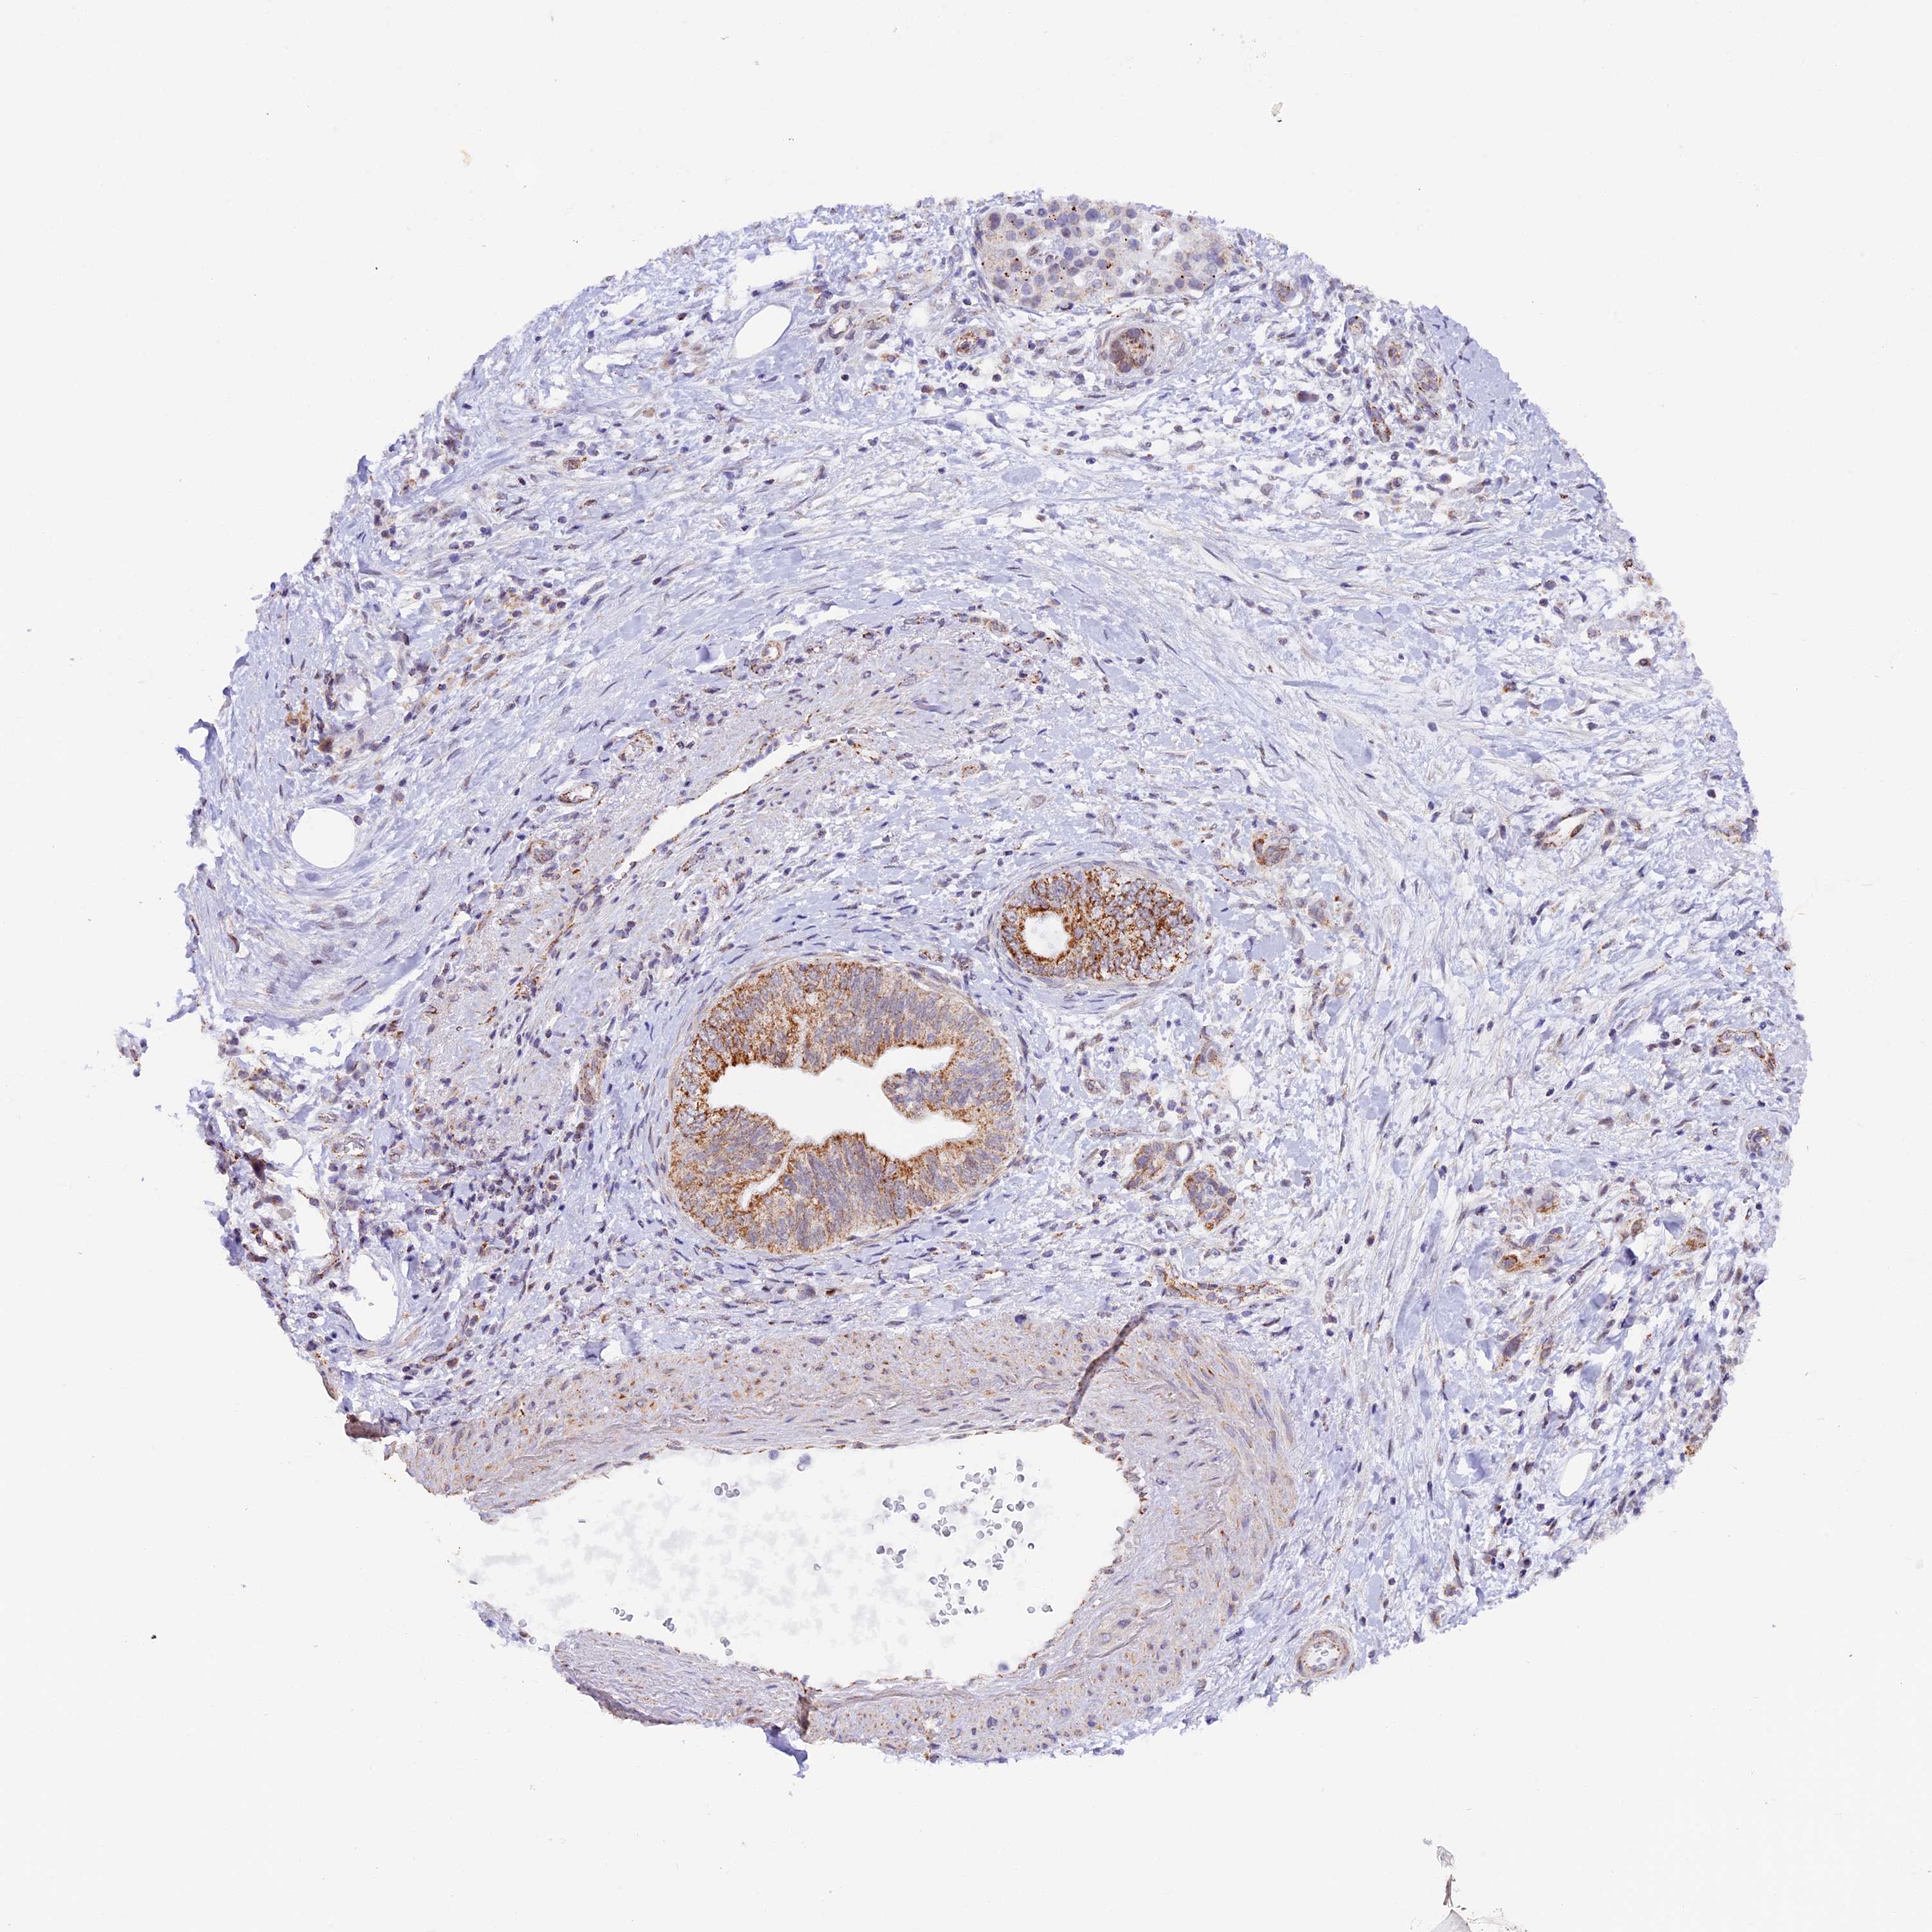

PANCREATIC CANCER - Protein expressioni

A mouse-over function shows sample information and annotation data. Click on an image to view it in a full screen mode. Samples can be filtered based on level of antibody staining by selecting one or several of the following categories: high, medium, low and not detected. The assay and annotation is described here.

Antibody stainingi

Antibody staining in the annotated cell types in the current human tissue is reported as not detected, low, medium, or high, based on conventional immunohistochemistry profiling in selected tissues. This score is based on the combination of the staining intensity and fraction of stained cells.

Each image is clickable and will lead to virtual microscopy that enables deeper exploration of all samples and also displays staining intensity scores, fraction scores and subcellular localization as well as patient and tissue information for each sample.

Antibody HPA040648

Staining

High

Medium

Low

Not detected

Intensity

Strong

Moderate

Weak

Negative

Quantity

>75%

75%-25%

<25%

None

Location

Nuclear

Cytoplasmic/membranous

Cytoplasmic/membranous,nuclear

Adenocarcinoma, NOS